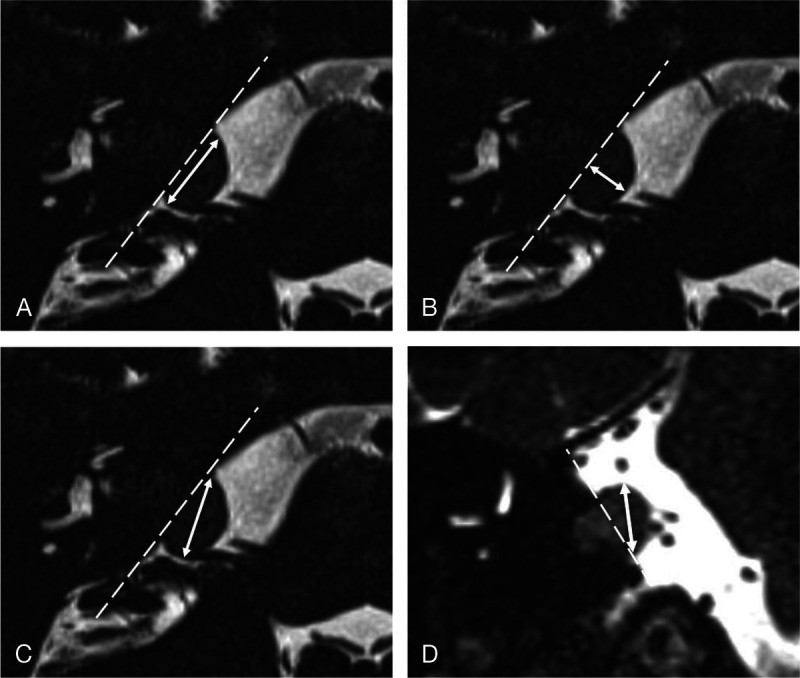

Methods: Six experts (neurosurgeons, otorhinolaryngologists, and radiologists) involved in VS management, from two tertiary referral centers, measured linear extrameatal VS tumor size parallel and perpendicular to the petrous ridge, and as maximum axial and maximum coronal diameter. Inter- and intra-rater reliability were evaluated using the intraclass correlation coefficient (ICC). The repeatability coefficient was computed for each measurement direction. Fleiss' kappa was used to determine the degree of agreement on tumor growth.

Results: Reliability between raters was significantly excellent (ICC >0.9) across all measurement directions, with the highest ICC observed for measurements parallel to the petrous ridge (ICC, 0.974; 95% CI, 0.957-0.986). Good or excellent reliability was achieved in 95.8% of all intra-rater measurements, with predominantly higher ICC scores for measurements in the coronal plane. Fleiss' kappa for interrater variability of determining tumor growth was highest and substantial for measurements parallel to the petrous ridge 0.672 (95% CI, 0.546-0.799).

Conclusion: Linear measurements of VS parallel to the petrous ridge yield excellent interrater reliability and the most favorable repeatability coefficient. Good to excellent intra-rater reliability across all measurement directions was observed. The most accurately defined tumor growth was obtained comparing measurements parallel to the petrous ridge. We recommend measurements parallel to the petrous ridge as the standard linear method for evaluating VS and growth.